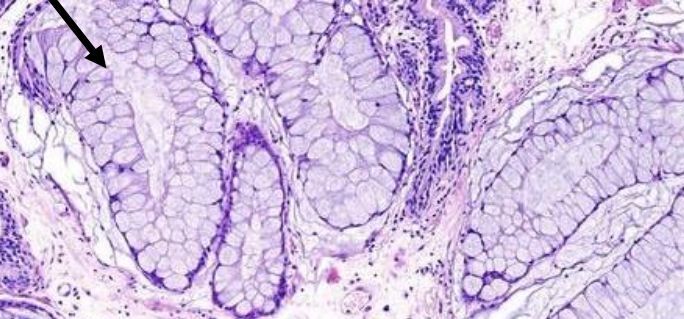

Von Brunn nests

Invaginations of the surface urothelium into underlying lamina propria. Normal urothelium thickness & cytology. Round shape (not infiltrative), uniform size

You should be thinking urothelial carcinoma if instead there are many small nests of irregular size that are stacked on-top of one another.